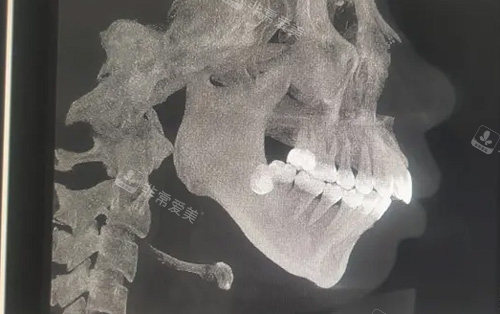

术前检查:患者需要进行齐全的身体检查,包括口腔检查、影像学检查等,以确定颌骨的具体情况和身体状况是否适合手术。

手术设计:医生会根据患者的面部特征和需求,结合影像学资料,设计出较佳的手术方案。

手术方案包括颌骨的调整位置、角度和幅度等。

首先,通过口腔内切口暴露颌骨,然后根据手术方案对颌骨进行截骨、移动和固定等操作。